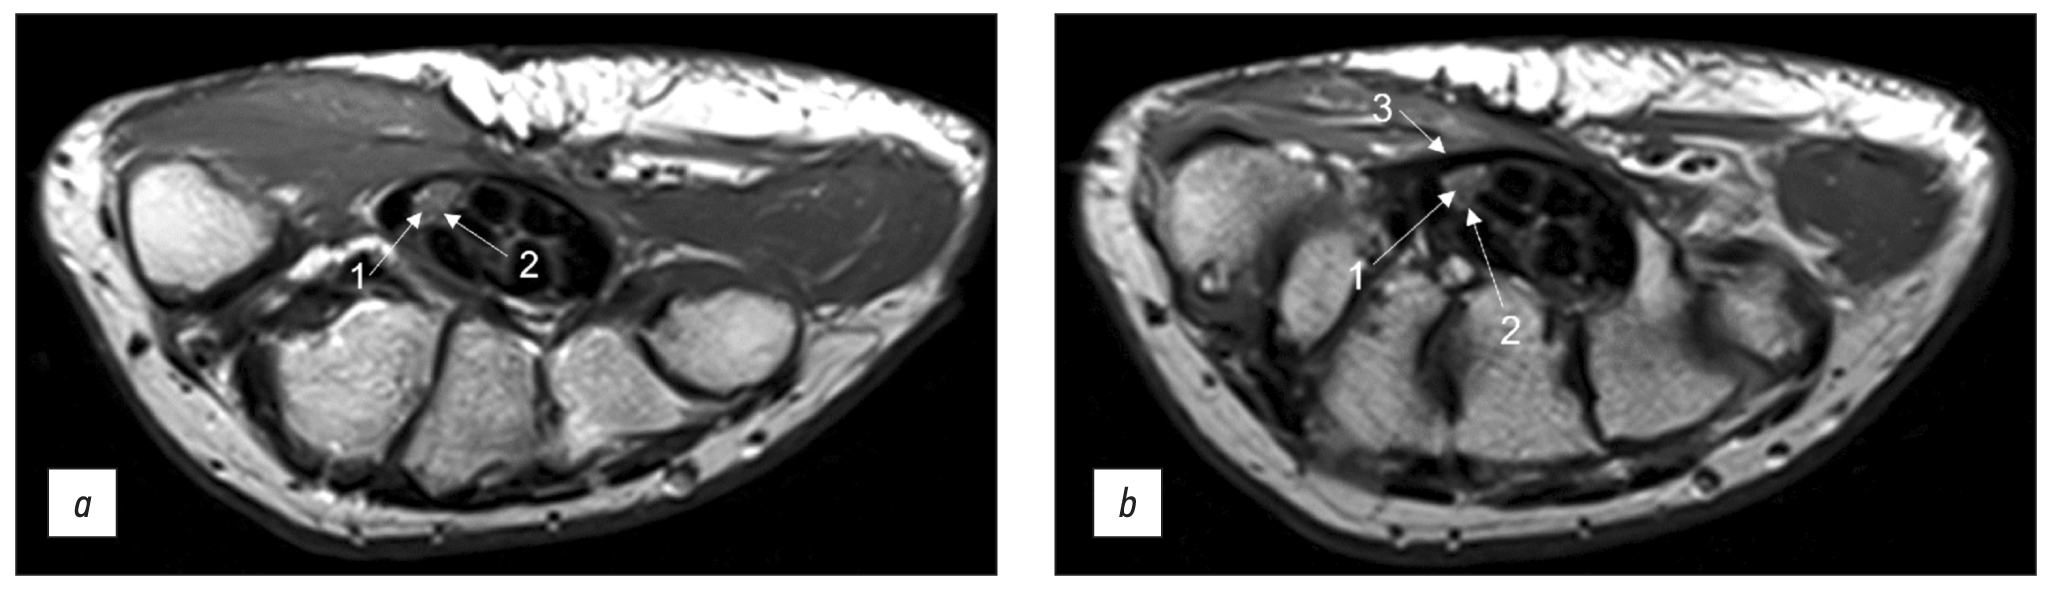

Fig. 2. Magnetic resonance imaging of the hand in T2 mode in a patient with carpal tunnel syndrome. An axial projection: (a) at the level of proximal epiphyses of metacarpal bonesand (b) at the level of distal parts of the capitate bone (1: individual fascicles as part of the median nerve, 2: epineurium, and 3: flexor retinaculum with a thickness of up to 1.29 mm).